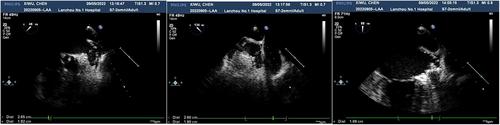

To assess the guiding role of transesophageal echocardiography (TEE) intraoperatively and its evaluative function postoperatively during left atrial appendage occlusion (LAAO) in patients with non-organic heart disease (NOHD).

In this retrospective observational study, a total of 48 patients with NOHD who underwent LAAO in the Department of Cardiology at The First People's Hospital of Lanzhou City from April 2020 to September 2022 were recruited. TEE findings during and after the procedure, cardiac chamber size, and cardiac function parameters at different surgical stages, postoperative occlusion efficacy, and complications were recorded. The application value of TEE in LAAO for patients with NOHD was evaluated.

Comparative analysis TEE-measured the maximum diameter of the LAAO (22.37 ± 3.86 mm) was significantly smaller than X-ray angiographic measurement (23.45 ± 4.22 mm; p < 0.05). One month after radiofrequency ablation, TTE revealed a statistically significant reduction in left atrial diameter (p < 0.05). Four cases (8%) exhibited minor peri-device leak (< 3 mm), and no major complications occurred.

TEE shows significant application value for monitoring anatomical changes, guiding device sizing, and detecting peri-device leaks during and after LAAO for patients with NOHD.